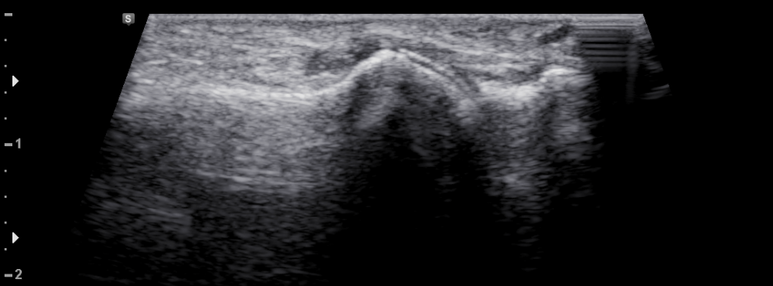

환부 관절의 연골면에 고음영의 요산 침착이 관찰됨 (double contour sign)